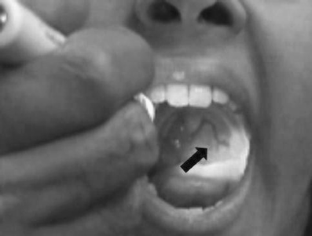

Ataxia telangiectasia (A-T) typically presents with early-onset progressive cerebellar ataxia, oculomotor apraxia and later, oculo-cutaneous telangiectasia. Extrapyramidal symptoms, apart from chorea, are rare. In this paper, we report a case of A-T with an atypically mild and slowly progressive disease course. Although by history there was mild gait clumsiness in early childhood, the leading problem was that of dystonia with onset at age 15, in the absence of gross gait imbalance or ocular motor apraxia. Dystonia was generalized and with prominent oromandibular involvement. Unusually, a leash of telangiectasia was present on the posterior pharyngeal wall, while other features frequently associated with A-T were absent.

There is prominent craniocervical dystonia with torticollis to the right and oromandibular involvement with intermittent tongue protrusion which interferes with her speech. When keeping the arms outstretched, there is mild dystonia of the hands. There is no ataxia on the finger nose test. Her gait is narrow-based and there is no difficulty with tandem gait or standing on one foot. Oral examination demonstrates telangiectasia on the left posterior pharyngeal wall. Her eye movements are normal without oculomotor apraxia. (MPG 5.88 MB)